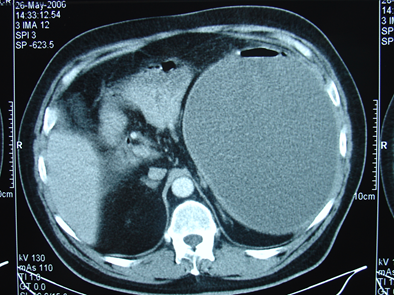

- Kontrastlı KT və ya MRT standart müayinədir, şişi və yayılma dərəcəsini müəyyənləşdirilməsində önəmlidir.

- Görüntüləmdə: erkən arterial fazada contrast tutan və venoz fazada yuyulan, MRT-də hipointens, ətraf toxumalara invaziv, böyüməyə meylli, baş nahiyyəsində yerləşərək xoledoxu və pankreatik axacağı genişləndirən (“iki axacaq simptomu”) törəmə